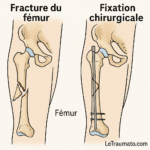

Options chirurgicales : arthroscopie, prothèse

Dans les cas avancés d’arthrose ou de lésions irréversibles, une prothèse totale du genou peut être envisagée. Elle permet de retrouver une vie normale sans douleurs nocturnes.